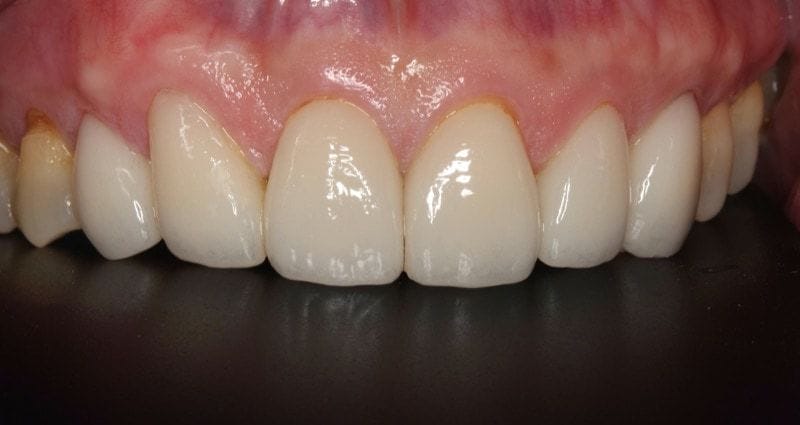

圖示:使用六顆數位全瓷貼片修復完成的牙齒近照,大幅改善前牙美觀

前牙用六顆全瓷貼片黏著修復後,Mr.Hsieh對治療結果滿意度很高。治療前後,從口腔、牙周健康、咀嚼功能穩定到前牙美觀改善。似乎從牙齒的改變,感覺整個人的外貌都顯得逆齡,甚至皺紋還變比較少呢!